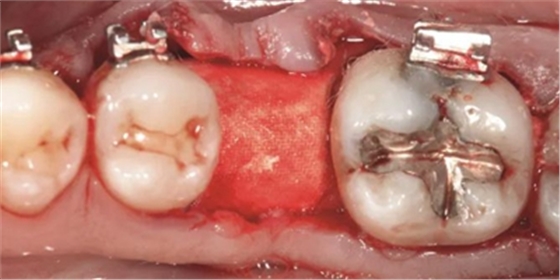

圖2a.病例1中,同期牙槽嵴增量和右下第一磨牙種植位點(diǎn)加速磨牙直立。術(shù)前臨床檢查顯示修復(fù)空間小、牙槽嵴吸收

圖2b.增量時(shí),在受區(qū)和右下第二磨牙遠(yuǎn)中進(jìn)行牙槽嵴去皮質(zhì)術(shù)